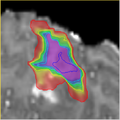

We have developed a probabilistic non-rigid registration framework where we characterize the posterior distribution over deformations with a MCMC method. In practice, a large number of deformations are drawn from the posterior distribution. From the set of deformation samples, we can estimate the most likely deformation as well as the uncertainty of the deformation.

The objective for the Project Week is to developing a command line module that can take the large set of deformation samples and generate useful marginal summarizes/visualizations of the registration uncertainty, e.g. marginal distribution of a biopsy point after registration.

1. A VTK class for generating marginal probability maps of deformed surface models.